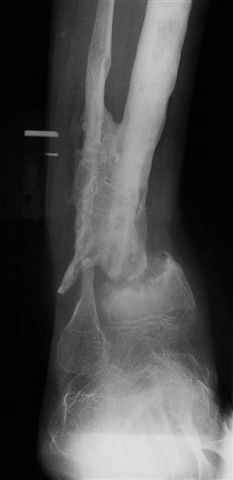

The case: Женщина 24 лет non union дистальной тибии с укорочением 7cm.

Все началось с перелома голени лет 8 тому назад. Остеомиелит - Илизаров в Kentucky, USA (деталей нет) и полтора года тому назад перелом средней трети тибии (1). Наложен унилатеральний фиксатор. Перелом зажил, но образовался стержневой остеомиелит дистального стержня. Потом нон юнион. В настоящий момент нет клинических признаков инфекции. Раны зажили.(2) Нон юнион подвижный и есть незначительное движение в голеностопе. Укорочение 7см. (3) Хотел бы знать мнение участников Форума. Благодарю. Nikolaj Wolfson, West Virginia, USA